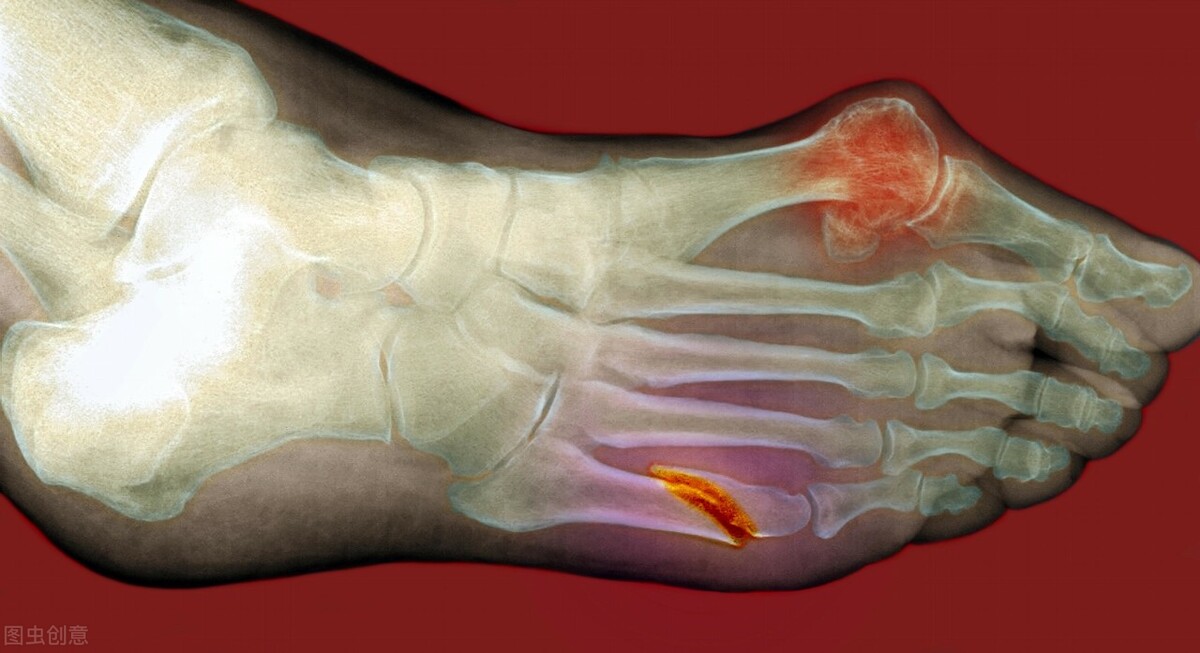

要讨论痛风能不能根治,那就需要了解下痛风是什么?从现代医学的角度看,痛风是一种代谢性疾病,是因为体内的尿酸过高,沉积到关节上形成尿酸结晶,引起关节肿胀,无菌性发炎的一种关节炎症。

现代医学认为,治疗痛风要从降尿酸入手,常见的非布司他、别嘌醇、苯溴马隆这些药物都是降低体内尿酸含量的药物,也都应用在临床上。而在急性期发作时,会应用一些非甾体抗炎药如布洛芬、塞来昔布等消炎止痛,缓解症状。